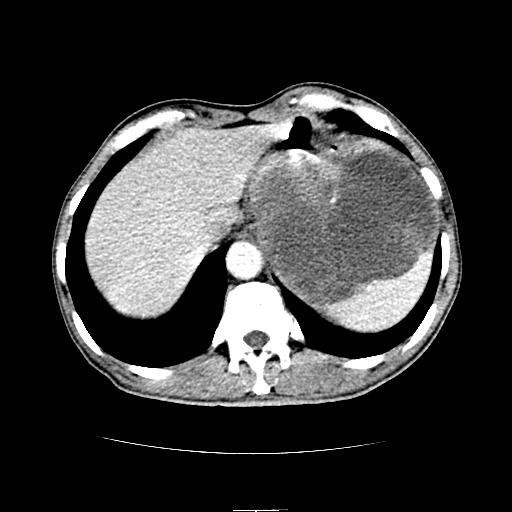

标题: CT6969:腹部,某男 34岁,腹痛治疗半月无效 [打印本页]

标题: CT6969:腹部,某男 34岁,腹痛治疗半月无效

左上腹胃、脾及胰腺间巨大囊性占位性病变,内见多数薄隔,有轻度强化,明显占位效应。左肾见一小囊肿。

考虑:1、左上腹巨大囊肿(可能来源于胰腺)。

2、左肾小囊肿。

左上腹胃、脾及胰腺间巨大囊性占位性病变,内见多数薄隔,有轻度强化,明显占位效应,胰腺及左肾结构清楚,明显向后下方推压 移位。左肾见一小囊肿.多考虑:1 网膜巨大囊肿。2 左肾小囊肿。

1胃脾胰之间一巨大囊性影,胃明显向前推移,胰体尾部似肥大,考虑囊性影来源于胰腺(假性囊肿?)2左肾小囊肿。

左上腹囊性占位,与胰腺分界不清,考虑起源于胰腺可能。

左上腹囊性占位,虽与胰腺分界不清,胰尾似乎受压前移,病灶最大截面并不在胰腺水平,考虑来源于网膜可能性大吧,应再详细追问病史.